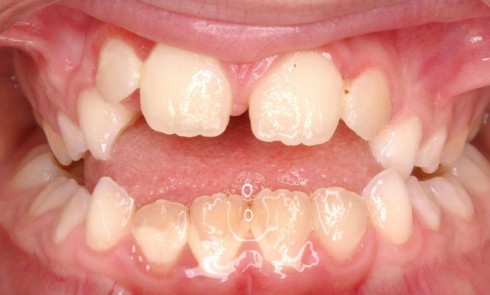

Article réservé à nos abonnés Gestion orthodontico-chirurgicale d’un cas de béance et importance de la prise en charge fonctionnelle

Les béances dentaires sont des malocclusions difficiles à traiter. Les troubles fonctionnels sont souvent à l’origine du problème, et leur...